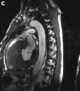

Anderson syndrome